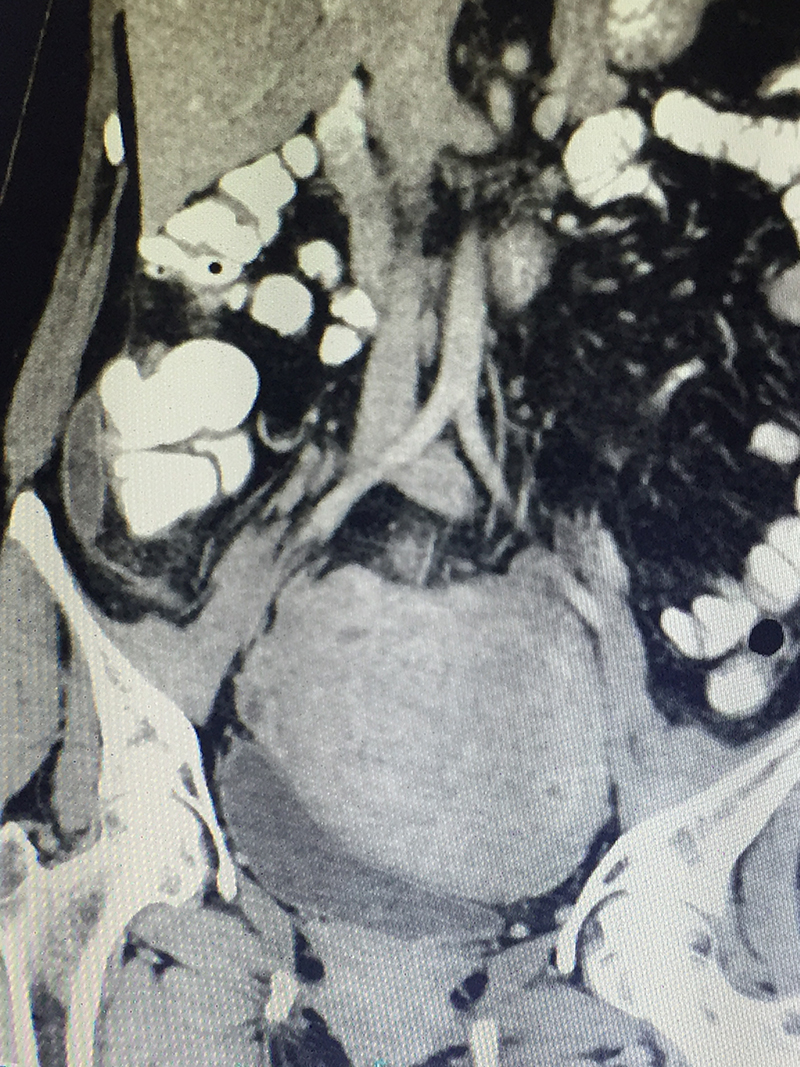

50 year old lady with acute abdominal pain in the right lower abdomen, vomiting and fever was diagnosed with acute appendicitis. Preliminary blood investigations & ultrasonography corroborated the diagnosis. A CT scan of the abdomen and pelvis was done to confirm the diagnosis & look for complications like perforation & abscess. An acute appendicitis with localized perforation & infected fluid collection was observed. She also had a large fibroid in her uterus. As is our policy (most acute appendicitis patients are treated by laparoscopic surgery), patient underwent a laparoscopy. At the time of laparoscopy, a perforated gangrenous appendix was found with a large walled off pus collection in the abdomen. The huge fibroid made the surgery difficult since it kept on coming in the line of surgery. However the appendicectomy was successfully completed laparoscopically and patient was discharged on 4th postoperative day. Due to the existing infection, a hysterectomy for the fibroid was not performed at the same time. It was done later after few months.

When there is a clinical suspicion of acute appendicitis, he / she is subjected to blood (CBC / CRP) investigations and imaging study (Ultrasonography). Severe colitis / enteritis / mesenteric lymphadenitis, ileal perforation, intestinal tuberculosis, inflammatory bowel disease, colonic diverticulitis, pericolic appendagitis, Meckel’s diverticulum etcetera can have present with similar symptoms and signs. Some of these diseases can be managed with medicines alone. Hence a CT scan of abdomen and pelvis with oral and intravenous contrast is advised before any surgery is planned for appendicitis. CT scan not only confirms diagnoses, but also reveals complications like perforation, abscess etcetera or an alternative diagnosis or associated malignancy (as in elderly patients).